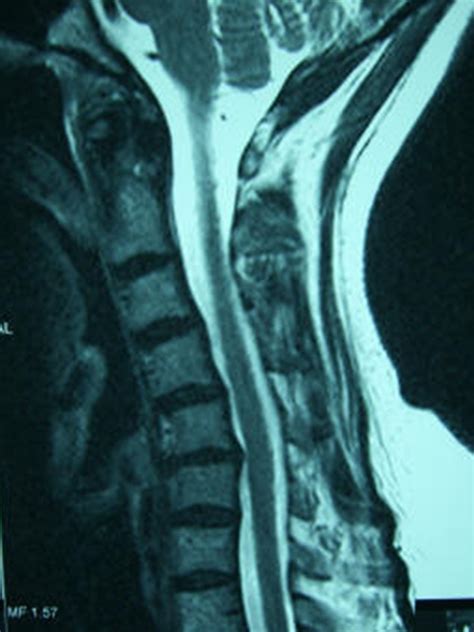

• Cervical Disc Herniation: When a disc in the cervical spine ruptures or bulges, it can compress nearby nerves, causing pain, numbness, and weakness in the neck, shoulders, and arms.

• Cervical Spinal Stenosis: This condition involves the narrowing of the spinal canal, which can compress the spinal cord and nerves, leading to pain, weakness, and difficulty with coordination.

• Medical Evaluation: Your surgeon will conduct a thorough medical evaluation, including a physical examination, imaging tests (such as X-rays, MRI, or CT scans), and possibly neurological tests.